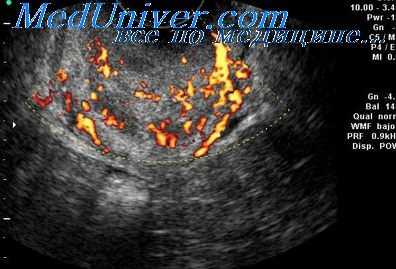

Б-я Н. 24 г. Цветовая допплерография развивающейся внематочной беременности. Цветовые пятна отражают кровообращение эмбриона (1) и в эктопически расположенном трофобласте (2)

У 14 пациенток (46,6 %) в проекции придатков матки визуализировалось полостное образование с неоднородной структурой и гиперэхогенным ободком, оно встречалось у пациенток с подозрением на трубную беременность, из них у 8 (57,2 %) — с наличием умеренного количества свободной жидкости в Дугласовом пространстве (эхографический признак прерывающейся трубной беременности). При цветовом допплеровском картировании в придатковом образовании определяется зона гиперваскуляризации, которая представляет собой трофобластический кровоток.